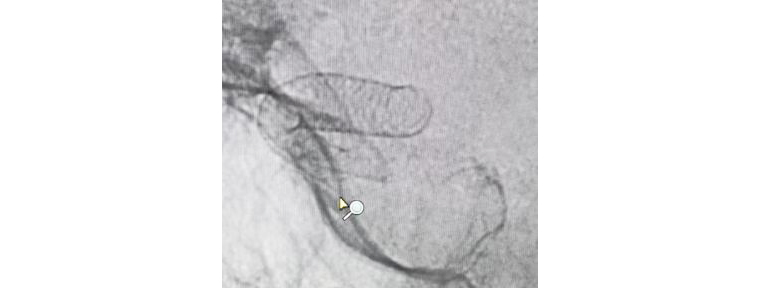

團隊人員術前充分準備,術中配合默契,支架順利釋放,造影觀察支架貼壁良好,瘤腔內造影劑滯留,載瘤動脈通暢,手術非常成功。術后兩天,患者平穩(wěn)出院,對治療效果很滿意。

支架成功釋放